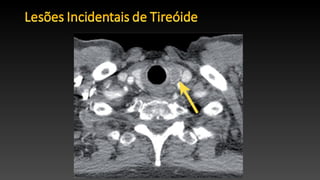

• Lesões de tireóide, muitas vezes são detectadas em exames de TC.

• Os nódulos são encontrados em aproximadamente 16%.

• A maioria das lesões de tireóide são benignas, 9%-11% são malignas.

• Em indivíduos eutireóidianos podem representar bócio multinodular

• TC confiavél em distinguir lesões benignas de malignas.

• TC não é confiável em distinguir cistos simples, cistos complexos e

nódulos sólidos.

• TC menor eficácia para avaliação quantitativa de nódulos.

• As diretrizes atuais de manejo de nódulos da tireóide são baseados

em características morfológicas ultrassonográficas.

• US não é confiável no diagnóstico de malignidade.

• Sua principal utilidade é na orientação de biópsias.